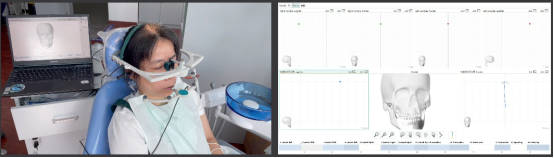

· 制作放射导板,进行数字化导板设计。

· 上下颌士卓曼360数字化导板 +预成临时修复体设计图。

· 士卓曼360导板包括:骨支持的基部导板 、牙支持的辅助导板 、就位于基部导板的种植导板 以及就位于基部导板的预成临时修复体组成。